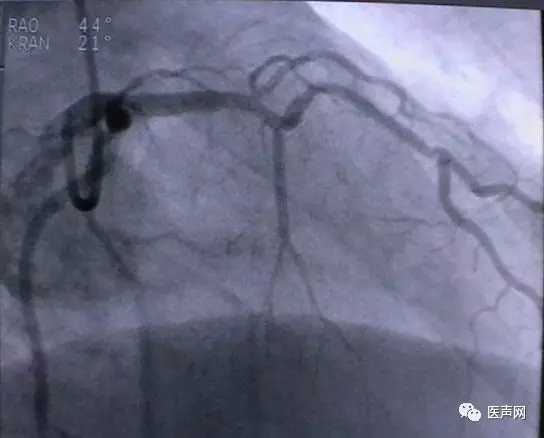

病例1: 冠脉搭桥术后,静脉桥CTO(CABG, VB-CTO)

箭头所示为第3个吻合点

(pre-PCI)

VB-对角支(jump)---LCX(jump)-PDA远端,第一个吻合以下完全阻断。

· 导引导管非常深置(Very very deep seating)(本例GC达CTO 第一吻合口前)(这是Dr. Lauer常用一招)

· 对侧造影

· 硬导丝(走得很远, 达PDA)

· 微导管,OTW 球囊.

当打通后,发生室速,电复律---出现无复流---室速---植入支架(TAXUS Liberte)

当导引导管非常深置(very very deep seating)时,你可以想象支持力有多大,永远不要忘记他做RCA-CTO时导引导管深插到RCA中段的例子。此病例实际上PDA未能开通,在6月28日 Dr. Lauer终于用类似方法打通了PDA。